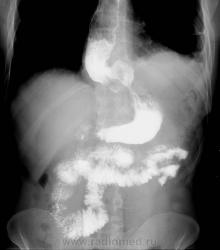

1.Анамнез у этого 45 летнего мужчины давний...болеет с детства, когда был первый раз оперирован на пищеводе...

2. Фундапликаций небыло, были попытки восстановить проходимость, но, как Вы заметили, неудачные.

3. Сейчас (1,5 мес назад) была проведена операция - наложение эзофагофундоанастомоза

Видимо проблемой была ахалазия пищевода. Решение озвучено.

Да, Петрович, первично была ахалазия, потом пару операций. Если Вам интересно,могу выложить результаты исследования и до операции.